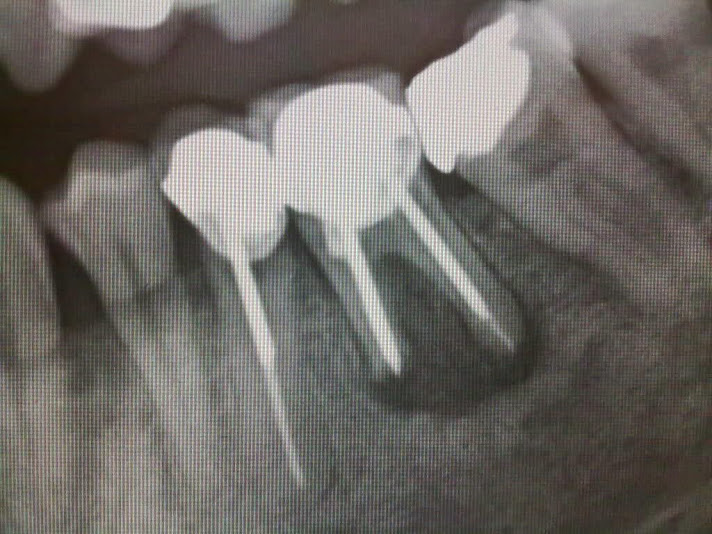

WebSe puede realizar endodoncia con infección. El tratamiento se Inicia con el drenado del absceso por la fistula, esto ayudara a que parte del el pus y exudados. WebLa endodoncia es un tratamiento que puede confundirse con el empaste, ya que, en principio, cumplen una función similar. Ambos tratamientos se emplean para curar. WebUna endodoncia es necesaria cuando se ha producido una caries muy profunda en la pieza con la consiguiente necrosis de la pulpa dental. También se utiliza para. WebPero, aunque la endodoncia permite salvar un diente enfermo para evitar su extracción, en ocasiones no se puede llevar a cabo y es inevitable la extracción del diente y la posterior. WebLa endodoncia se realiza para desinfectar los conductos infectados y eliminar el tejido dañado o "muerto" del interior de ellos. Es el tratamiento de elección para conductos. WebEl diente con endodoncia, es más frágil y por ello pasados unos meses se pone una funda para protegerlo y evitar fractura.. La causa es que a pesar de no haber nervio el hueso.

WebLa endodoncia se realiza para desinfectar los conductos infectados y eliminar el tejido dañado o "muerto" del interior de ellos. Es el tratamiento de elección para conductos. WebEl diente con endodoncia, es más frágil y por ello pasados unos meses se pone una funda para protegerlo y evitar fractura.. La causa es que a pesar de no haber nervio el hueso. WebAunque la endodoncia permita rescatar un diente enfermo para evitar su extracción, de vez en cuando no se puede hacer: Cuando la pieza dentaria presente una.